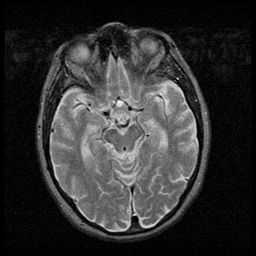

Huntington's Chorea, MR -- Slice #7

[Home][Help][Clinical] Slice 7